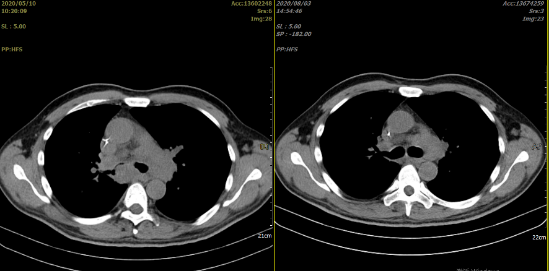

由于患者治疗中出现了进展,在当地参加了 CAR-T 细胞治疗的相关临床试验,在经过一疗程 R-CHOPE 方案桥接治疗及 FC 方案预处理后,患者于 2020 年 3 月接受了一次鼠源 CD19 CAR-T 细胞输注,输注后经历了 2 级 CRS 反应,随后在输注后 1 个月的早期评估 CT 中可见肿瘤明显缩小。

随后患者在 2020 年 4 月接受了 CD22 CAR-T 输注,作为序贯治疗。治疗后患者出现发热,胸闷,咳嗽以及间断的咯血。当地医院考虑 CRS 反应可能,给予相应的处理。CAR-T 细胞扩增情况具体不详。然而,在第二次 CD22 CAR-T 输注后的一个月,患者进行了 PET-CT 的评估,结果提示为肿瘤进展,如下图 3: